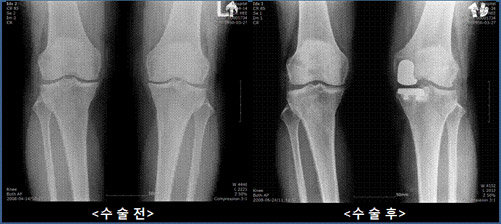

이러한 문제들이 있기 때문에 가급적 자기의 관절을 살려서 사용하고자 하는 연골 재생 치료가 각광을 받고 있으며, 인공관절이 필요하다면 무릎 전체를 다 갈아치우는 것 보다는 가능하면 손상된 부분만 교체를 하고 나머지 부분은 자기의 관절을 보존하는 부분치환술이 관심을 받고 있다. 초기의 부분치환술은 1950년대 무렵부터 시작되었으며 삽입물 자체의 성능 문제나 수술 술기의 부족 등으로 결과가 썩 좋지 않았다. 그러나 새로운 인공 관절 기술들이 발전하면서 1970년대 후반에 현재 사용하고 있는 것과 비슷한 부분치환술용 인공 관절이 개발되면서 결과가 비약적으로 좋아지기 시작했고 현재 미국에서는 전체 무릎 인공 관절 치환술의 약 5%정도를 차지한다고 한다.

무릎 관절 부분치환술의 장점은 무릎의 건강한 부분을 보존함으로써 본래의 자기 무릎 기능을 최대한 보존할 수 있다는데 있다. 이렇게 함으로써 정상 무릎 관절의 역할을 보존하여 관절 운동 각도도 좋아질 뿐만 아니라 위치 감각도 유지할 수 있다. 절개 부위도 기존 인공 관절 수술이 10-15cm 정도의 절개가 필요하였지만 부분치환술은 약 7-8cm정도의 절개로도 수술이 가능하다. 절개가 작고 부분적으로만 교체하기 때문에 수혈량도 줄어 기존 수술에 비해 절반정도의 수혈로도 충분하고 수술 후 기능 회복도 빨라서 수술 다음날 보행이 가능하고 입원 기간도 전치환술에 비하여 훨씬 줄어들게 된다. 또한 무릎 관절 운동 범위도 좋아서 수술 후 쪼그려 앉을 수 있을 정도로 가동성 또한 좋다.

반면에 단점도 있다. 첫 번째는 수술 술기 자체가 어려워서 인공 관절 수술의 경험이 풍부한 의사가 집도를 해야 한다. 김용찬 원장은 “수술시 절개 부위가 작기 때문에 수술 시에 골 절제 그리고 하지 정렬을 맞추기가 기존의 인공 관절 수술에 비해 어렵다”며, “시술 시에 실수가 일어날 가능성이 기존 인공 관절 수술보다 많기 때문에 주의해야 한다”고 말했다. 두 번째는 모든 관절염 환자에서 할 수 있는 것이 아니라 관절의 여러 부분 중 어느 한쪽만 손상이 온 환자에서만 시행할 수 있다. 류마티스 관절염이나 변형이 심한 퇴행성 관절염의 경우에는 시술이 불가능하다. 인공 관절 중에서는 비교적 조기 치료에 속한다고도 할 수 있다.

무릎 인공 관절 부분치환술의 도입 및 성공은 현대 의료계의 발전에 힘입은 것이며 평균 수명의 연장에 따라 최대한 자기 관절을 살려서 치료하고자 하는 최근 경향을 반영하는 것이다. 연골은 손상되어 아픈데, 인공 관절 전치환술을 하기에는 부담스럽고 아직은 때가 아니라고 생각이 된다면 문제가 생긴 부분만 교체하는 부분치환술을 고려해 볼 필요가 있다. 적절한 환자에게 경험 많은 의사가 시행한다면 환자의 만족도도 점점 높아질 것으로 생각되며, 앞으로 점점 이 수술은 늘어날 것으로 생각된다.